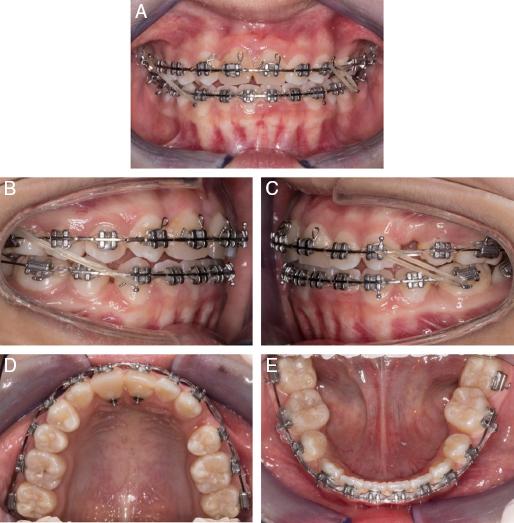

Figure 3.